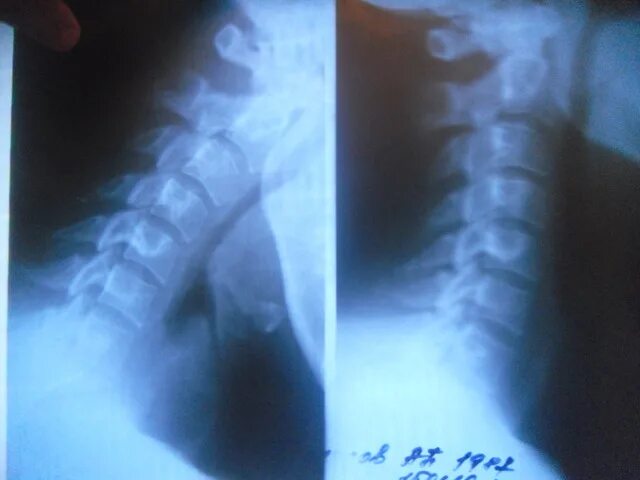

Аномалия в шейном отделе